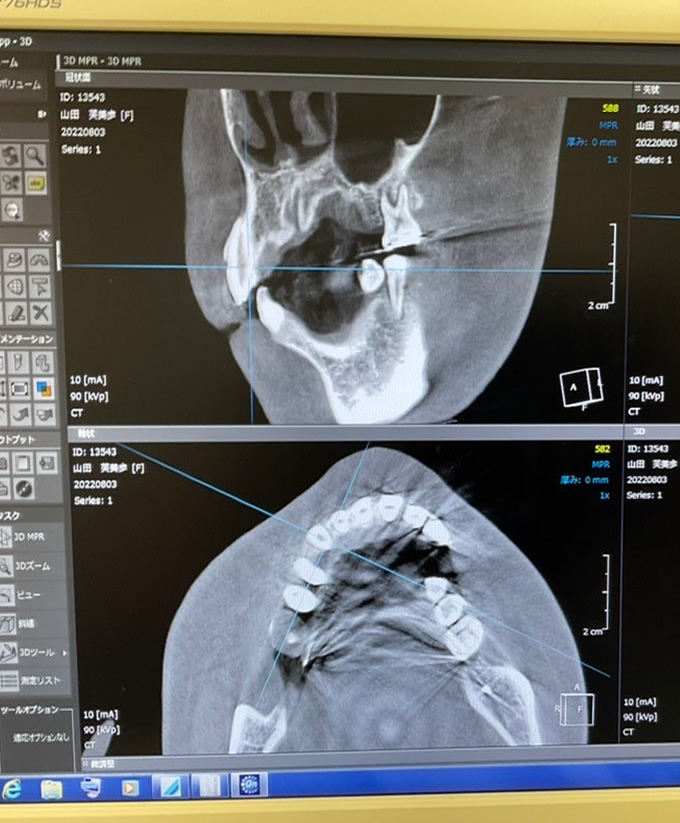

マウスピース矯正において、治療前の診査・診断が非常に大切になります。当医院では患者さまの口腔環境に応じて、顎関節の検査、噛み合わせ検査、顎の骨の大きさや位置関係、歯の角度などの分析を行うセファロ分析、最新の口腔内3Dスキャナーを導入し、矯正治療の事前シミュレーションなど様々な診査、分析を行います。

この診査・診断、分析は、豊富な経験と知識が必要になります。治療計画通りに歯が動くのか、表面的な審美性だけでなく、歯根部分の正常移動やかみ合わせはどうかなど、様々な角度から治療前に診査、診断を行います。